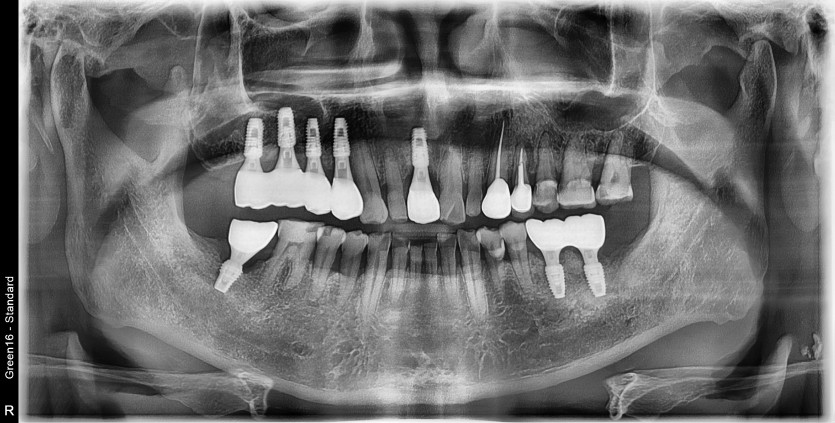

#37 타원 임플란트 제거 후

임플란트 수술+치조골이식술 시행하였습니다.